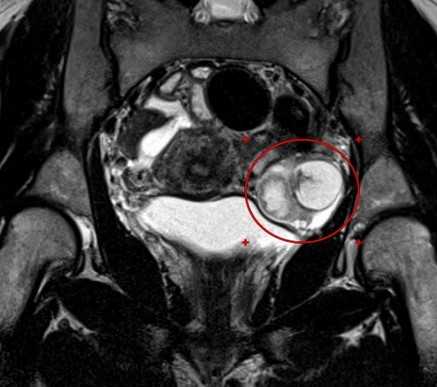

МРТ малого таза в сагиттальной плоскости. По задней стенке матки — интрамурально-субсерозная лейомиома (круг) с признаками гиалиновой дегенерации.